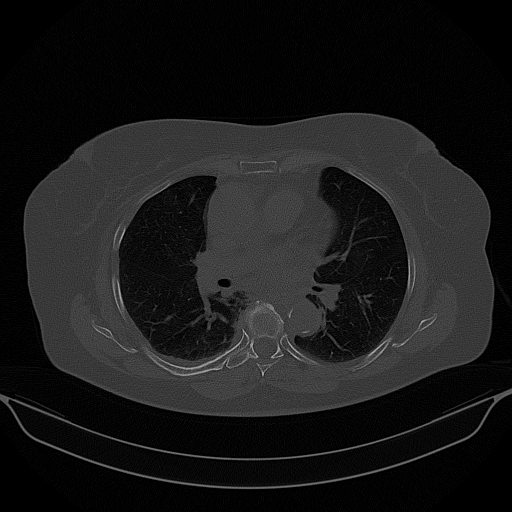

Reconstructed NATIVE CT scan (cycle consistency)

Full window (WL 1023.5, WW 4095 β†’ Low βˆ’1024, High +3071)

Lung window (WL -600, WW 1500 β†’ Low βˆ’1350, High +150)